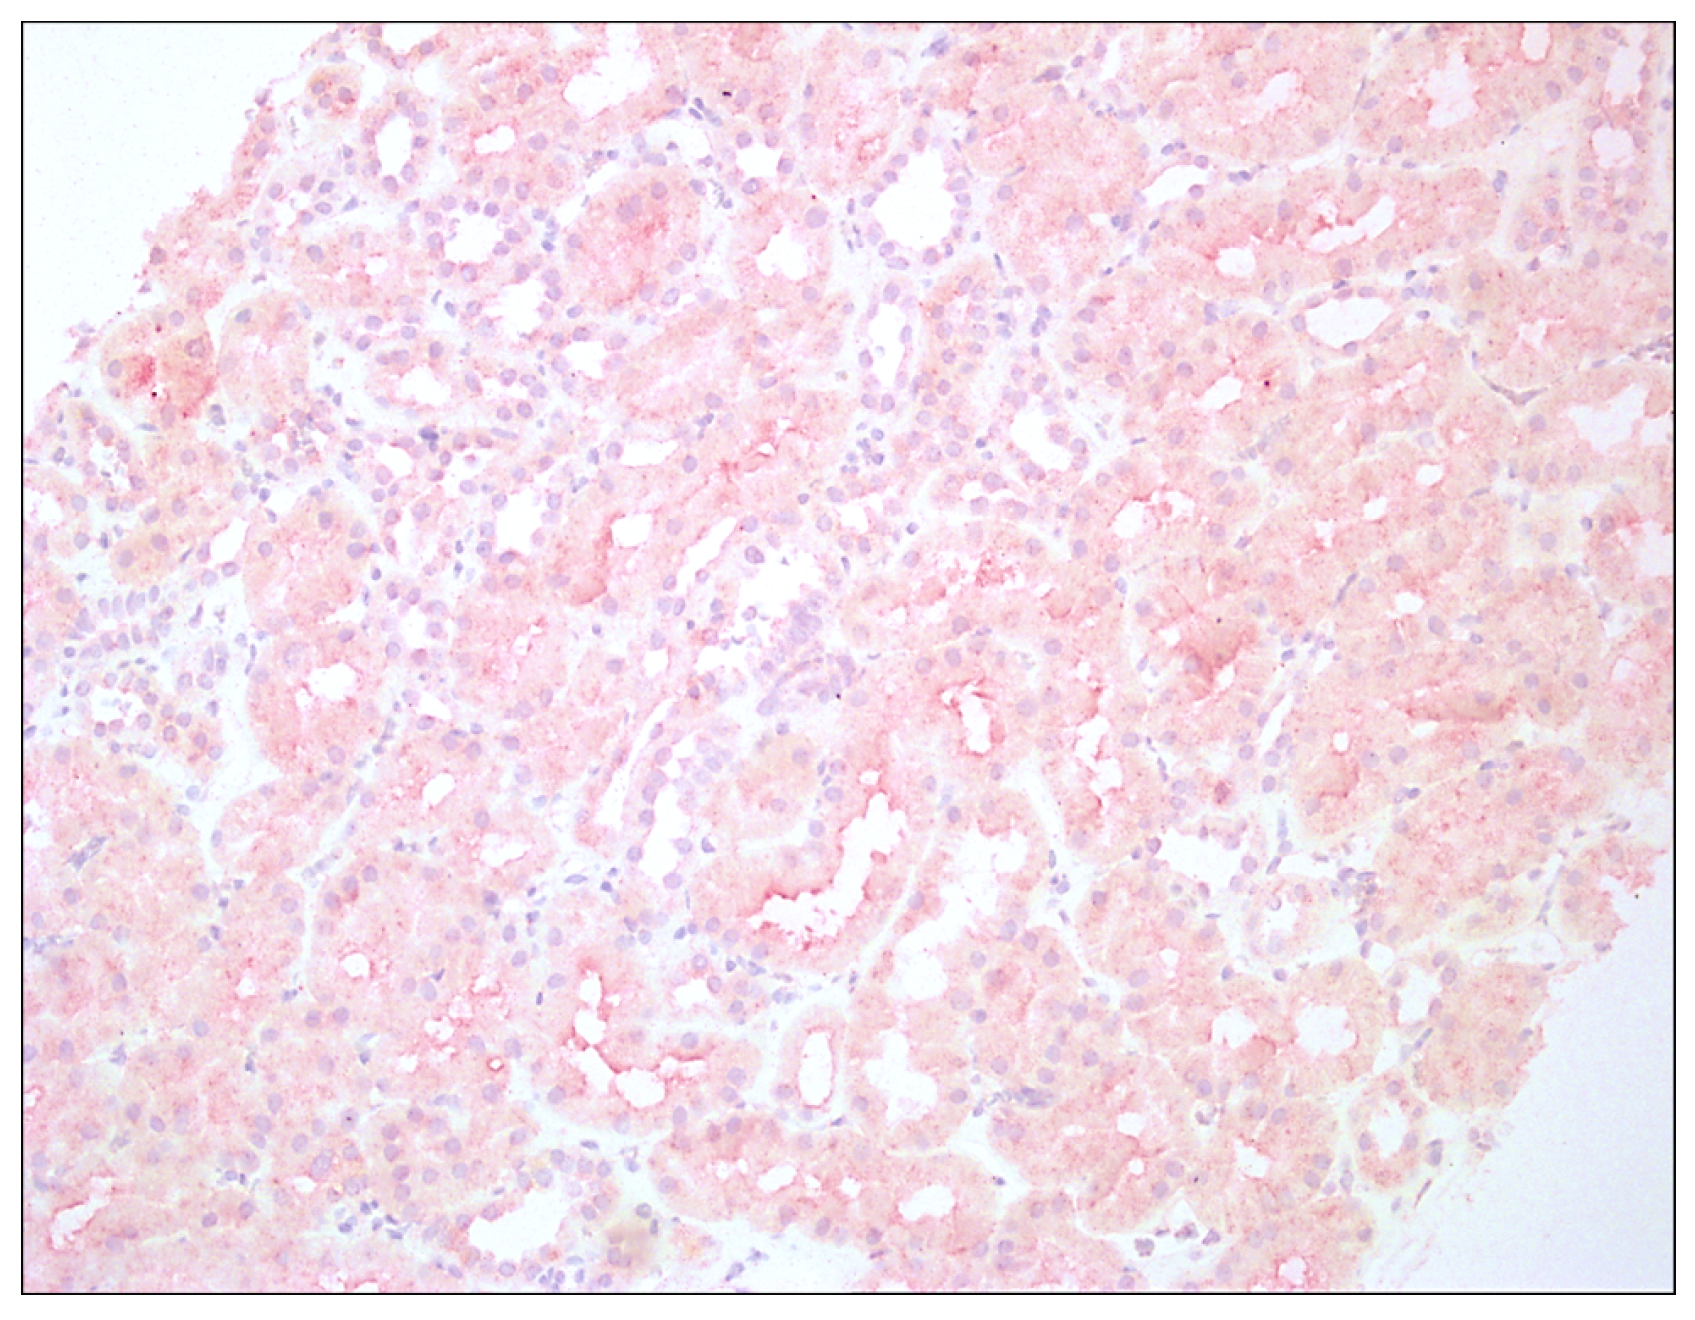

2.2. Histopathology and Staining Method

2.3. The Scoring System for IDO1 Expression